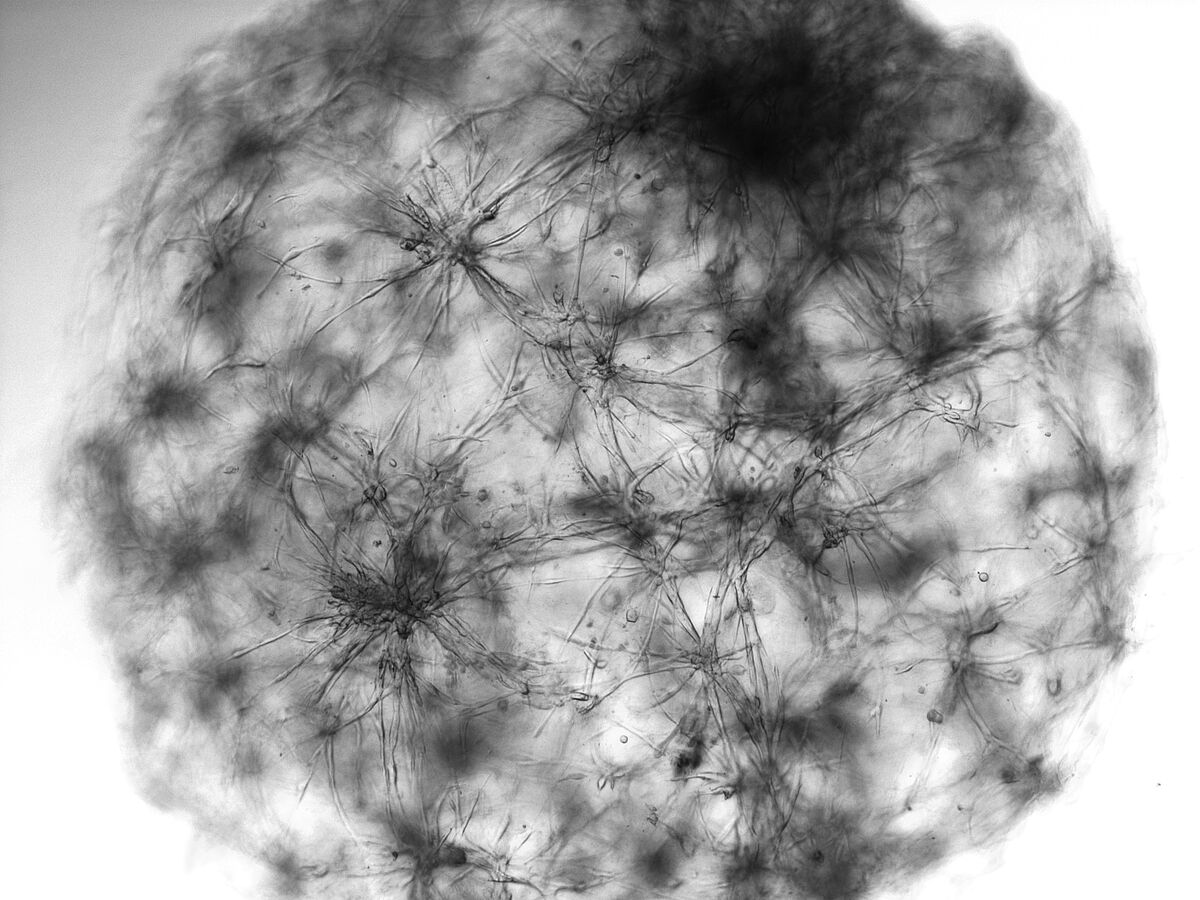

Stark vereinfacht beschrieben werden nun Kopien aus den frischen Gewebeproben gezüchtet. Konkret bedeutet es, dass die lebenden Tumorzellen der Patient:innen im Labor aufbereitet und in einer Matrix kultiviert werden. Diese Matrix ähnelt menschlichen Gewebestrukturen und ermöglicht so die Nachahmung der komplexen Umgebung eines Tumors. Zudem wird in der Matrix das Wachstum der Tumorzellen begünstigt und die Vermehrung nicht-krebsartiger Zellen begrenzt. So entwickeln sich die Tumorproben zu 3D-Zellkulturen, die, wie der Tumor selbst, räumlich organisiert sind und genomische, molekulare und phänotypische Merkmale des Tumors aufweisen.

In internationalen Studien konnte der Einsatz von Tumor-Organoiden für eine verbesserte personalisierte Therapie nachgewiesen werden und seit 2017 wird das Verfahren vom National Cancer Institute (NCI) als „Best-Practice-Approach“ empfohlen.